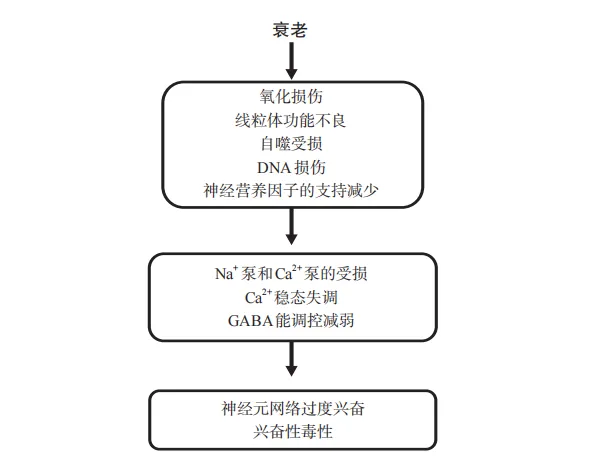

但也要小心,谷氨酸受体的过度激活会产生“兴奋性毒性”,这种毒性可以在癫痫发作、脑卒中和创伤性脑损伤时迅速发生,也可能在阿尔茨海默病、帕金森病等疾病中更隐蔽地发生。

阿尔茨海默病和帕金森病是两种常见的脑部神经退行性变性疾病,二者都涉及一种与谷氨酸受体过度激活有关的“慢性兴奋性毒性”,这是由患者大脑细胞能量代谢受损,同时伴有神经毒性蛋白的积累导致的。

当我们面临无法摆脱的压力时,神经元网络会被激活用来应对这些压力,但如果谷氨酸能神经元被过度激活,则会导致焦虑症的出现。